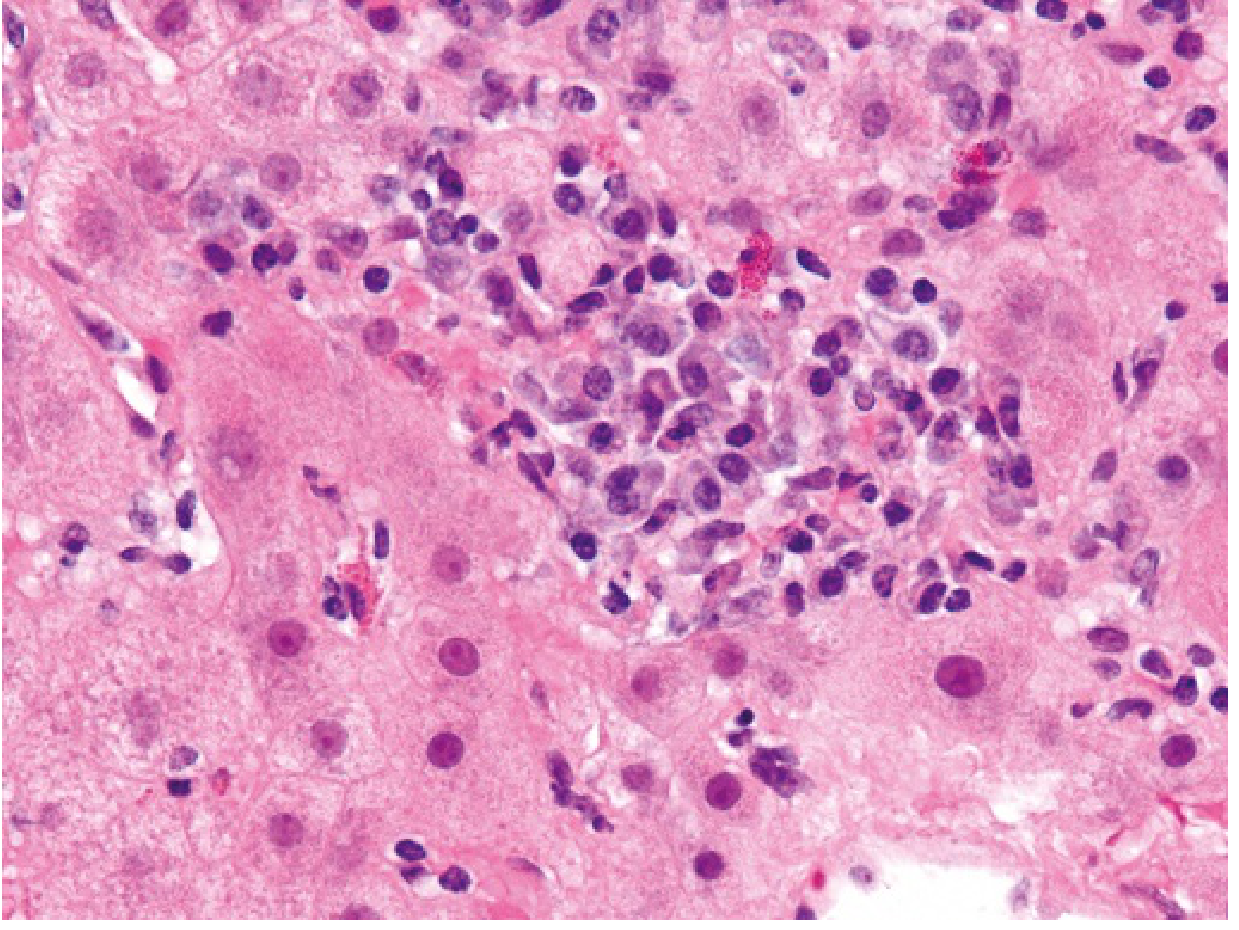

Histologically, acute viral hepatitis demonstrates:

• Portal area mononuclear infiltrates (predominantly T lymphocytes and plasma cells)

• Interface hepatitis with lobular disarray

• Hepatocyte ballooning degeneration and apoptotic (Councilman) bodies

• Focal hepatocellular necrosis

Chronic hepatitis adds periportal fibrosis, bridging fibrosis, and ultimately cirrhosis.

Acute hepatitis B liver biopsy showing dense portal mononuclear infiltrates, ballooning degeneration, and interface activity (H&E stain)

Acute viral hepatitis (hepatitis B): dense portal and lobular inflammatory infiltrate with hepatocyte injury on H&E biopsy.